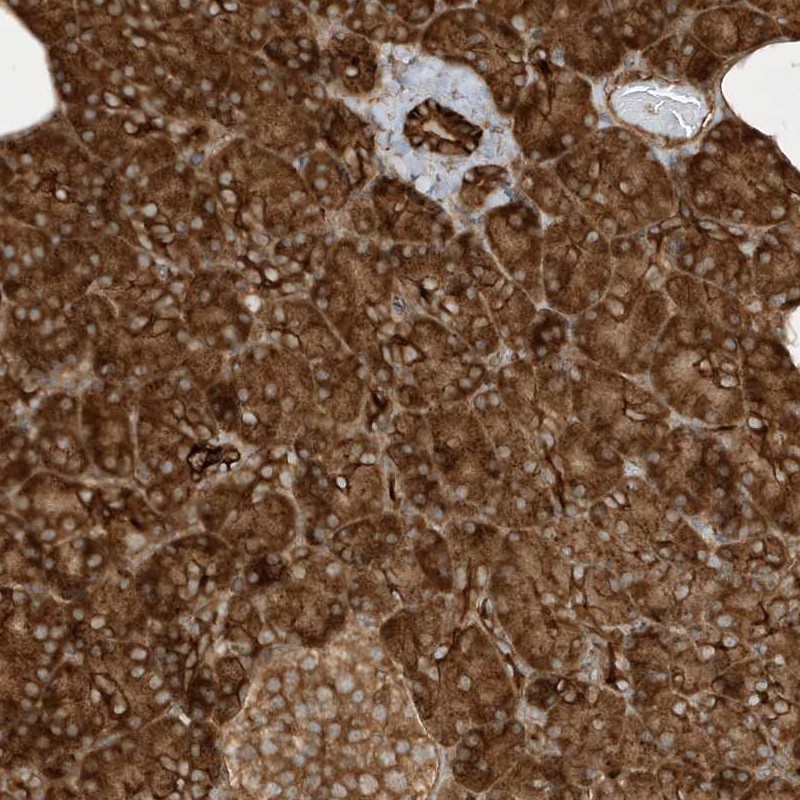

Immunohistochemical staining of human pancreas shows strong cytoplasmic positivity in exocrine glandular cells.